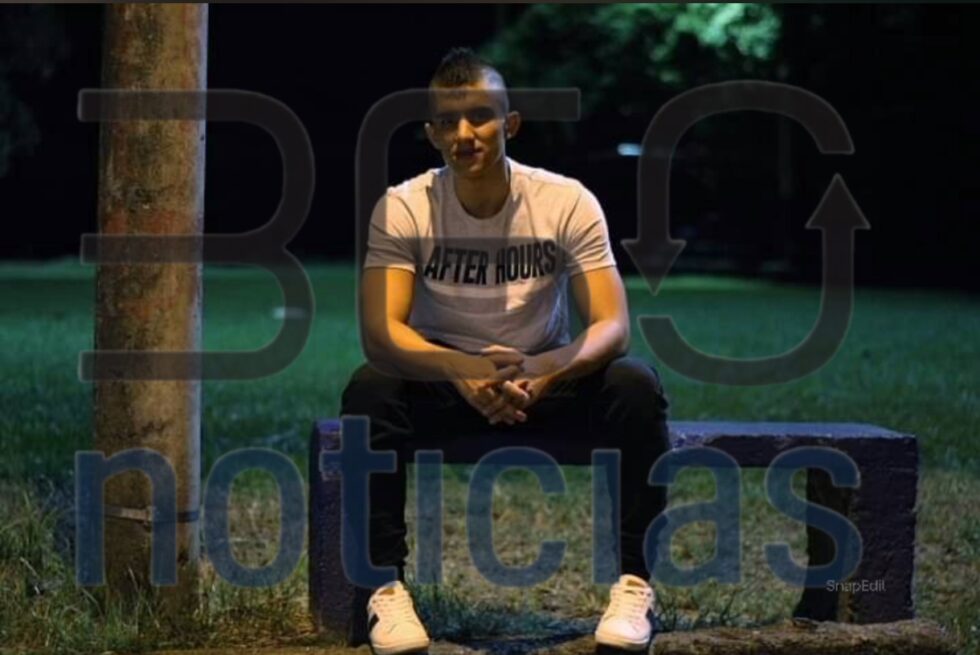

En Pereira, Miguel Ángel Martínez lleva cuatro años de lucha contra el sistema de salud. Hoy, una cirugía para corregir una fractura de fémur se convirtió en su peor pesadilla, ya que enfrenta graves complicaciones. Según él, por negligencia médica.

“Hasta el momento, me tendrían que hacer una cirugía nuevamente porque la pierna está llena de unos líquidos”, explico al joven evidentemente preocupado.